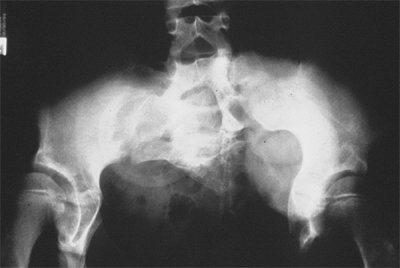

Figure 27.4

The radiographic appearance of coxa vara associated with spondylometaphyseal dysplasia in a 4-year-old child. (Courtesy of Perry L. Schoenecker.) |